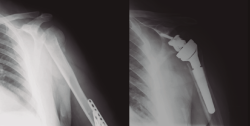

Protocolo rehabilitador en fracturas de húmero proximal quirúrgicas: osteosíntesis (Figura 8)

Figura 8. Radiografía de una fractura de húmero pre- y postosteosíntesis.

La RHB postoperatoria difiere según la clasificación de la fractura o según el sistema de osteosíntesis. En la revisión de la literatura realizada por Rosen et al.(4), no se obtuvieron conclusiones, aunque el tema fue muy poco discutido.

El protocolo que proponemos es básicamente el mismo que el descrito en las PHF no quirúrgicas, con las excepciones y consideraciones que se detallan a continuación (Tabla 1):